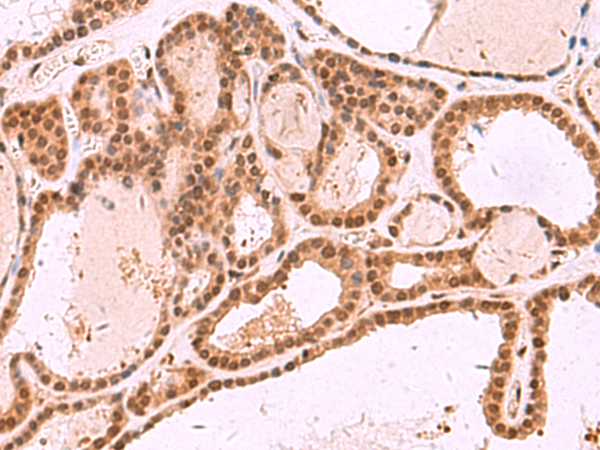

分类: 科研抗体货号: P11007别名: LSFC, GP130, LRP130, CLONE-23970应用: IHC反应种属: Human, Mouse, Rat